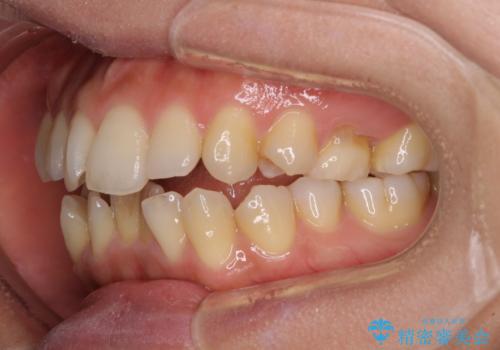

残存乳歯とオープンバイト インビザラインによる矯正治療

- 前歯のデコボコと咬み合わせを気にして来院された患者様です。

左上奥歯には乳歯が残存しており、後続永久歯は舌側に転位していました。

また、舌の突出癖の影響で上下前歯が接触していないオープンバイトとなっており、奥歯に負担のかかる咬み合わせとなっていました。

舌のトレーニングをしっかりと行ってくださり、前歯部のオープンバイトは大幅に改善されました。

もう少しでよりタイトに前歯が接触できそうでしたが、患者様がもう十分とのことで治療を終了しました。